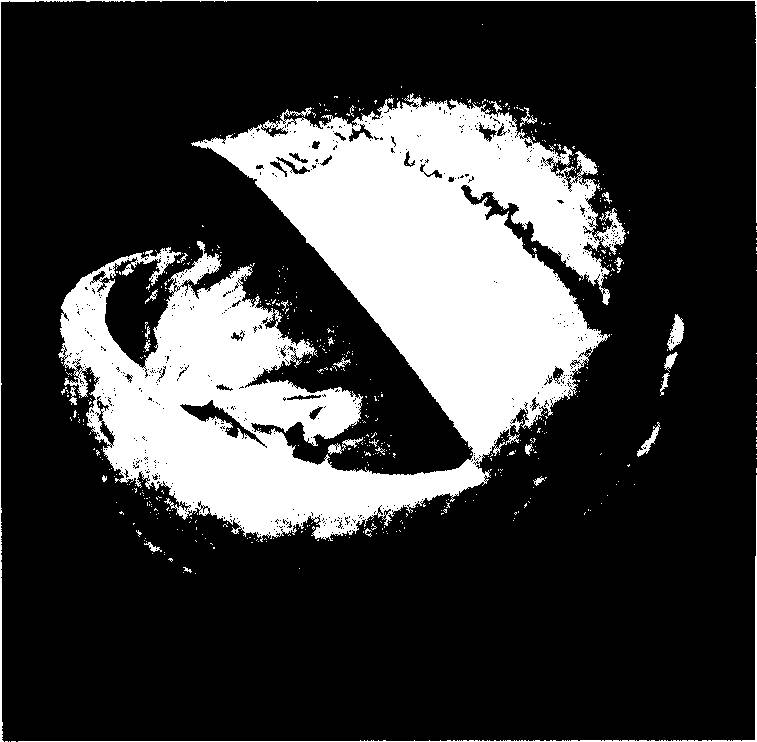

Исходя из нее, мы будем обречены признать главенство черепа над мозгом и некое фантастическое право двадцати трех его косточек по своему усмотрению диктовать мозгу, а через него – и всему организму, форму, функциональность и этапы развития. (илл.23)

Илл. 23. Кости черепа

Мозговой отдел. Непарные кости: є – os frontale (лобная); 2 – os occipitale (затылочная); 3 – os sphenoidale (клиновидная); 4 – os ethmoidale (решетчатая кость) (на фото не видна); 5 – vomer (сошник) (на фото не виден). Парные кости: 6 – os temporale (височная); 7 – os parietale (теменная); 8 – concha nasalis inferior (нижняя носовая раковина); 9 – os lacrimale (слезная) (на фото не видна); 10 – os nasale (носовая). Лицевой отдел. Парные кости: 11 – maxilla (верхняя челюсть); 12 – os palatinum (нёбная) (на фото не видна); 13 – os zygomaticum (скуловая). Непарные кости: 1 4 – mandibula (нижняя челюсть); 15 – os hyoideum (подъязычная) (на фото не видна).